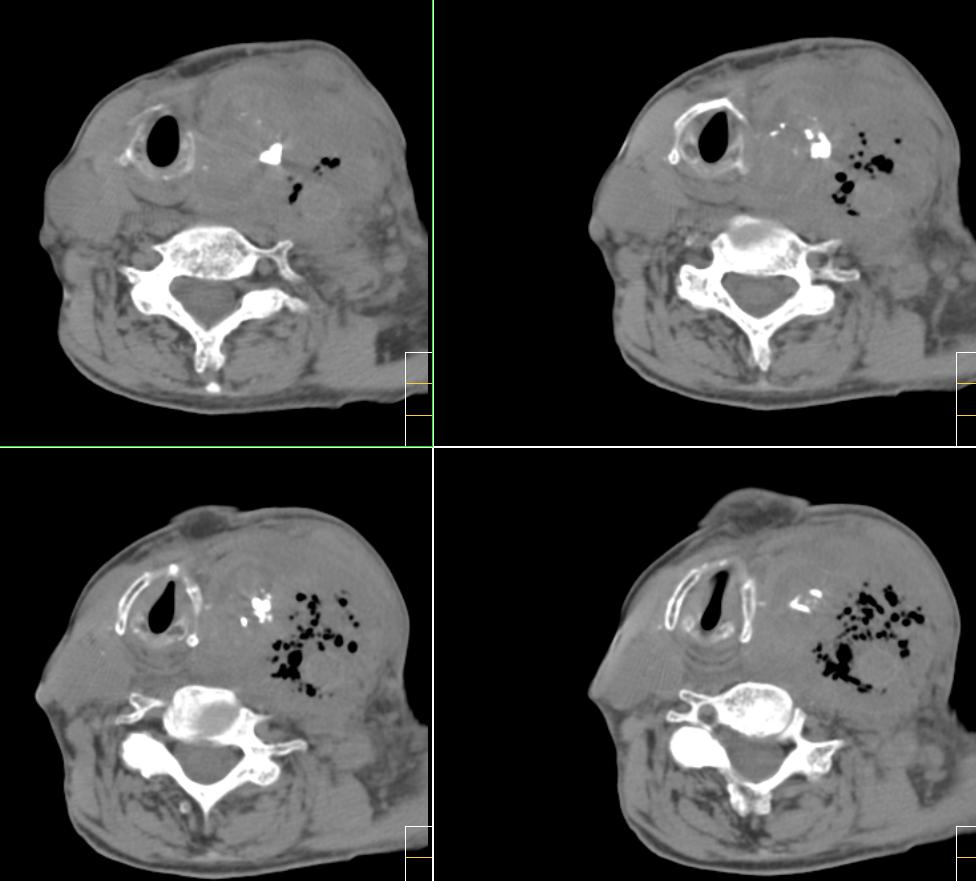

f、72y,左侧颈部发现包块及疼痛1周,彩超提示颈部血管破裂?

考虑1颈部脓肿侵蚀血管致血管瘤形成。2甲状腺左叶占位。

考虑颈部脓肿,并侵蚀血管后形成动脉瘤的可能性大;左侧甲状腺肿瘤.

软组织内积气来源为颈部产气菌感染所致.

除上诉考虑外,那么多而且不规则、不定形的钙化还应该想到有颈部畸胎瘤的可能性。顺着思路继续,颈部畸胎瘤继发产气菌感染,并在颈总动脉局部形成小脓肿且浸蚀到血管壁。

左颈部血管增粗,周围软组织肿胀模糊,内有蜂窝状积气影,左侧甲状腺增大,气管受压右移,气管软骨环未受侵。结合病史较短考虑:左颈部脓肿破裂并血管瘤形成,左甲状腺瘤。